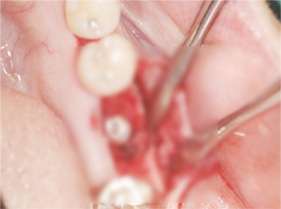

임플란트 식립

인공뼈 및 가가골 이식 (뼈 이식)

뼈의 재생을 유도 (골유도재생술)

잇몸 봉합 (3~5개월 후 완성)